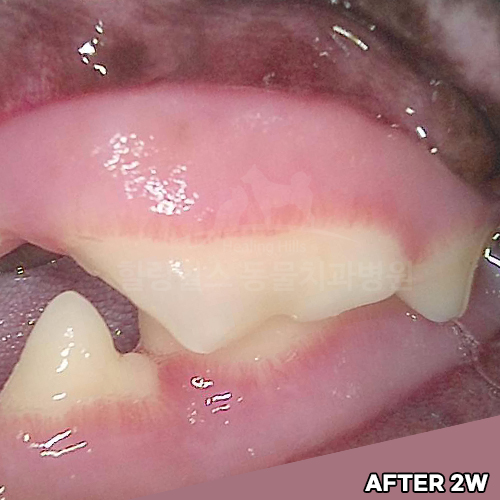

[신경치료 4개월 후 사라진 치근단농양!!]

샘플